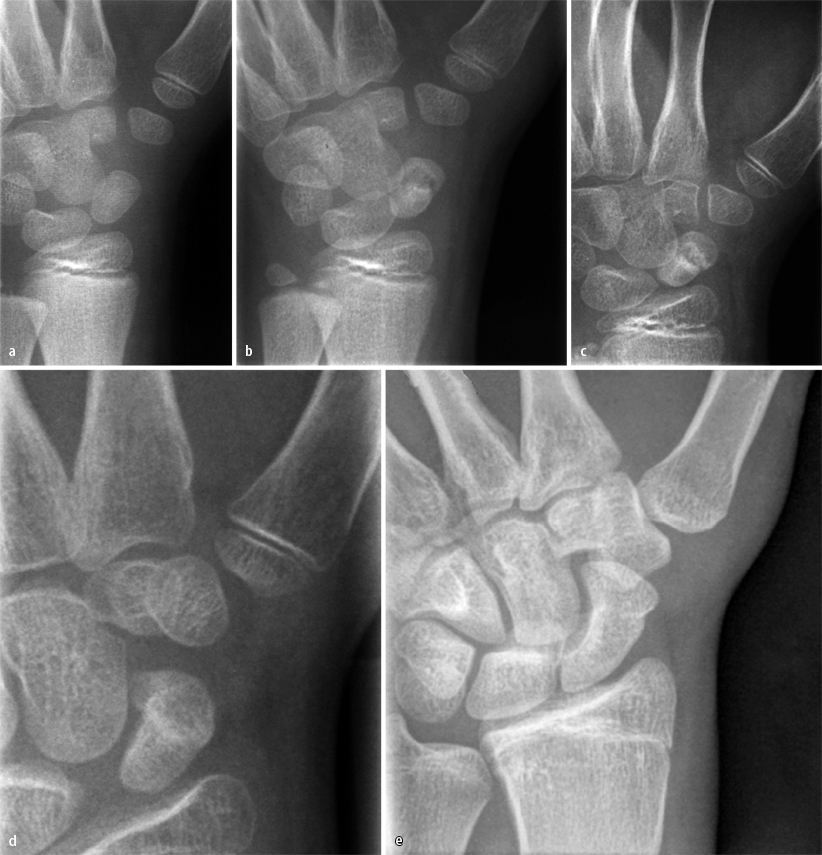

Die Bandersatzplastik Bei Lunotriquetraler Instabilitat Mit